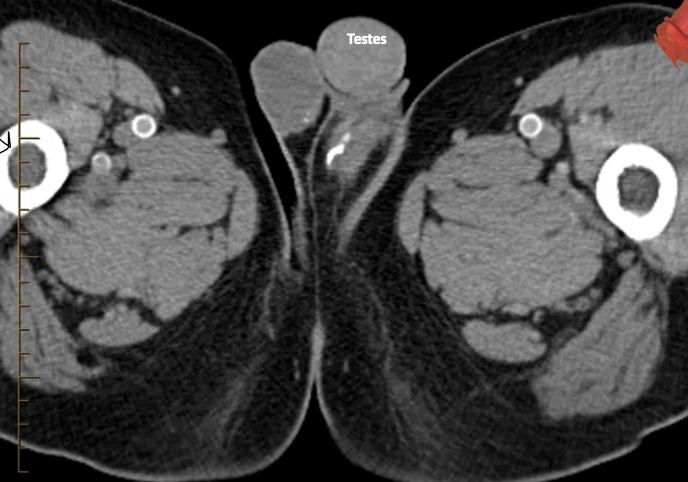

What type of imaging & view is this? And what abnormalities can we see

CT male pelvis, axial view

Calcification within the vascular structures; small bit of calcifications in vas deferes